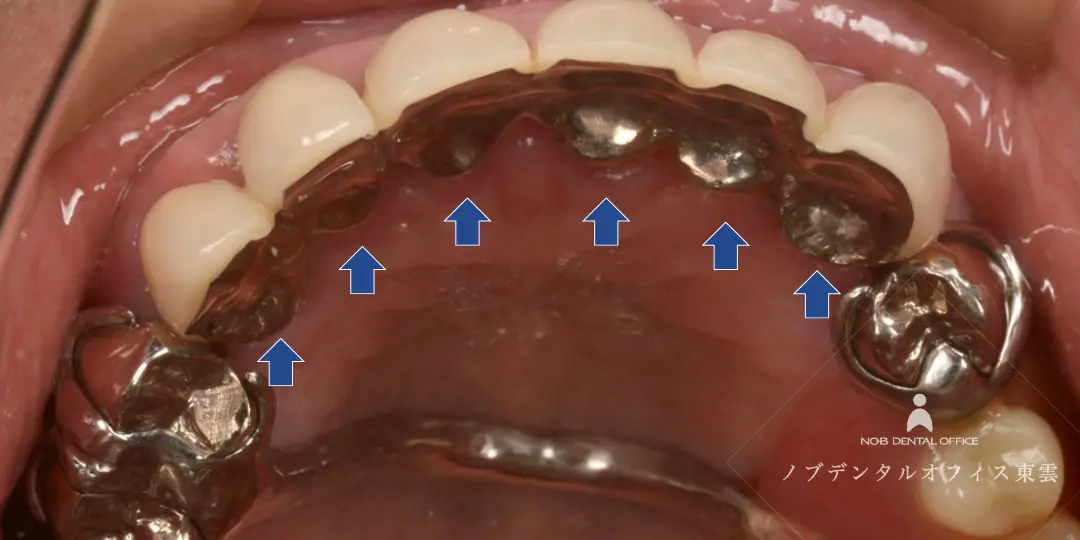

ブリッジの再治療をジルコニアで行った症例(40代女性)

右上の奥歯にすでに保険適用の金属のブリッジが入っていました。

| 治療 | ・根管治療の再治療 ・歯周外科処置(歯ぐきの形態修正) ・ジルコニアブリッジ |

| 費用 | かぶせ物の費用:143,000円×3本 保険適用 |

| リスク | ・経年的に摩耗が起こることがあります。 ・強い噛みしめや歯ぎしりにより、欠けたり外れる可能性があります。 ・歯ぐきの状態によっては境目が見えてくる場合があります。 ・清掃状態や生活習慣によっては境目から虫歯や歯周病が起こることがあります。 |